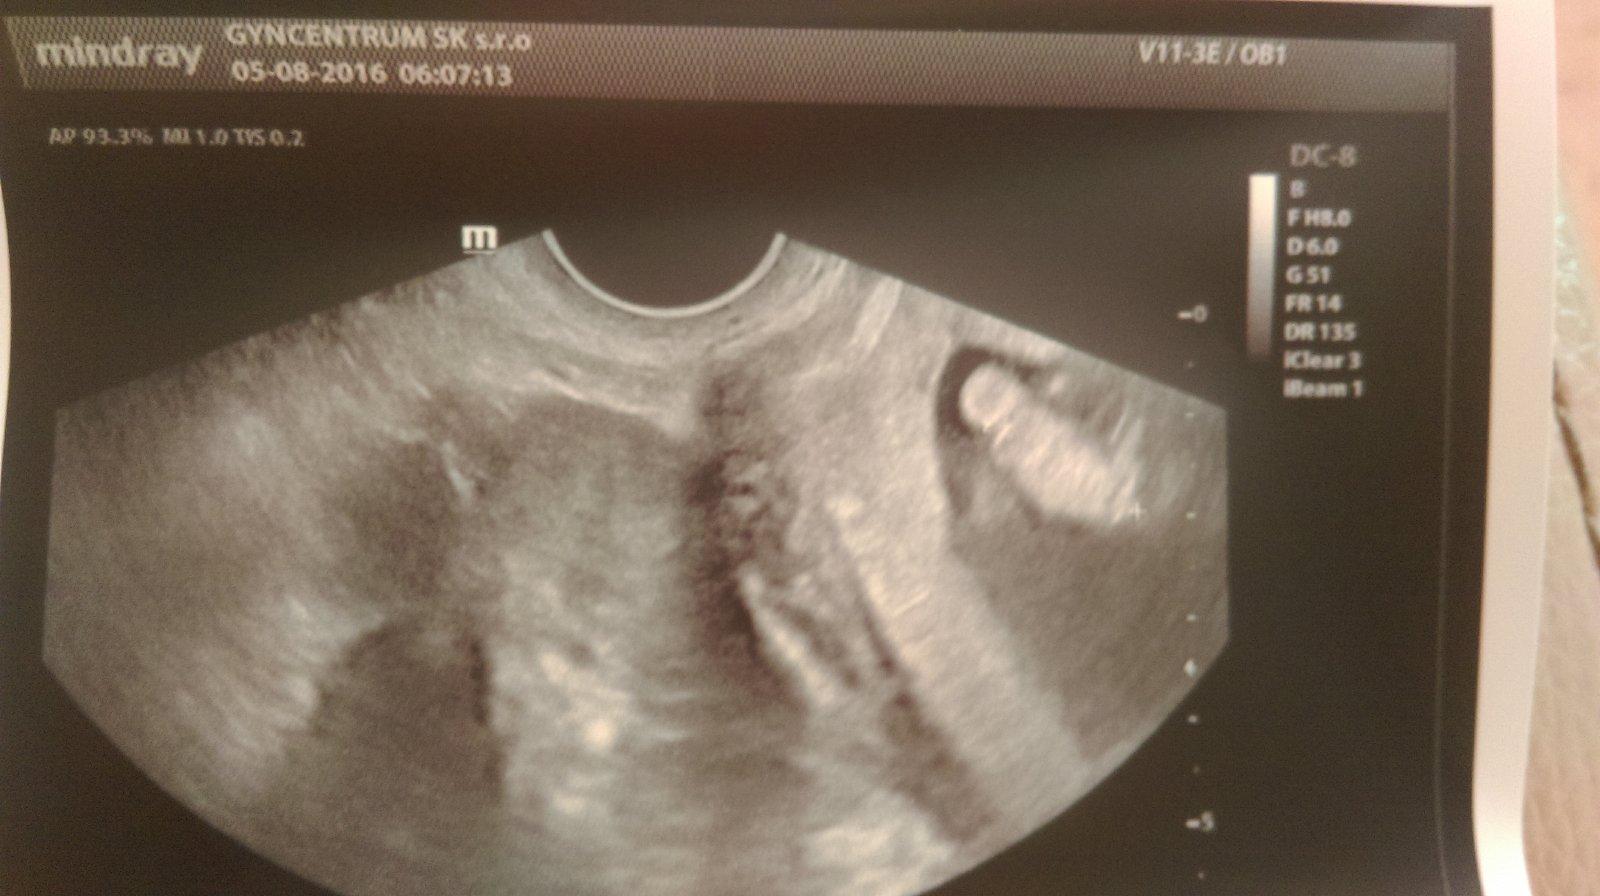

Baby otazka..predvcerom som bola na pohotovosti s krvacanim, nasadili mi ascorutin a dicynone. Uz nekrvacam, len vecer badam jemne hnede spinenie. Mam bolesti v podbrusku, nie krce, len bolesti. Cakam dvojicky, bude to tym ze sa maternica roztahuje dvojmo? 🙂